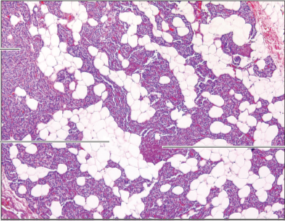

Q8. Which of the following histology images is not an endocrine structure?

Answer – D